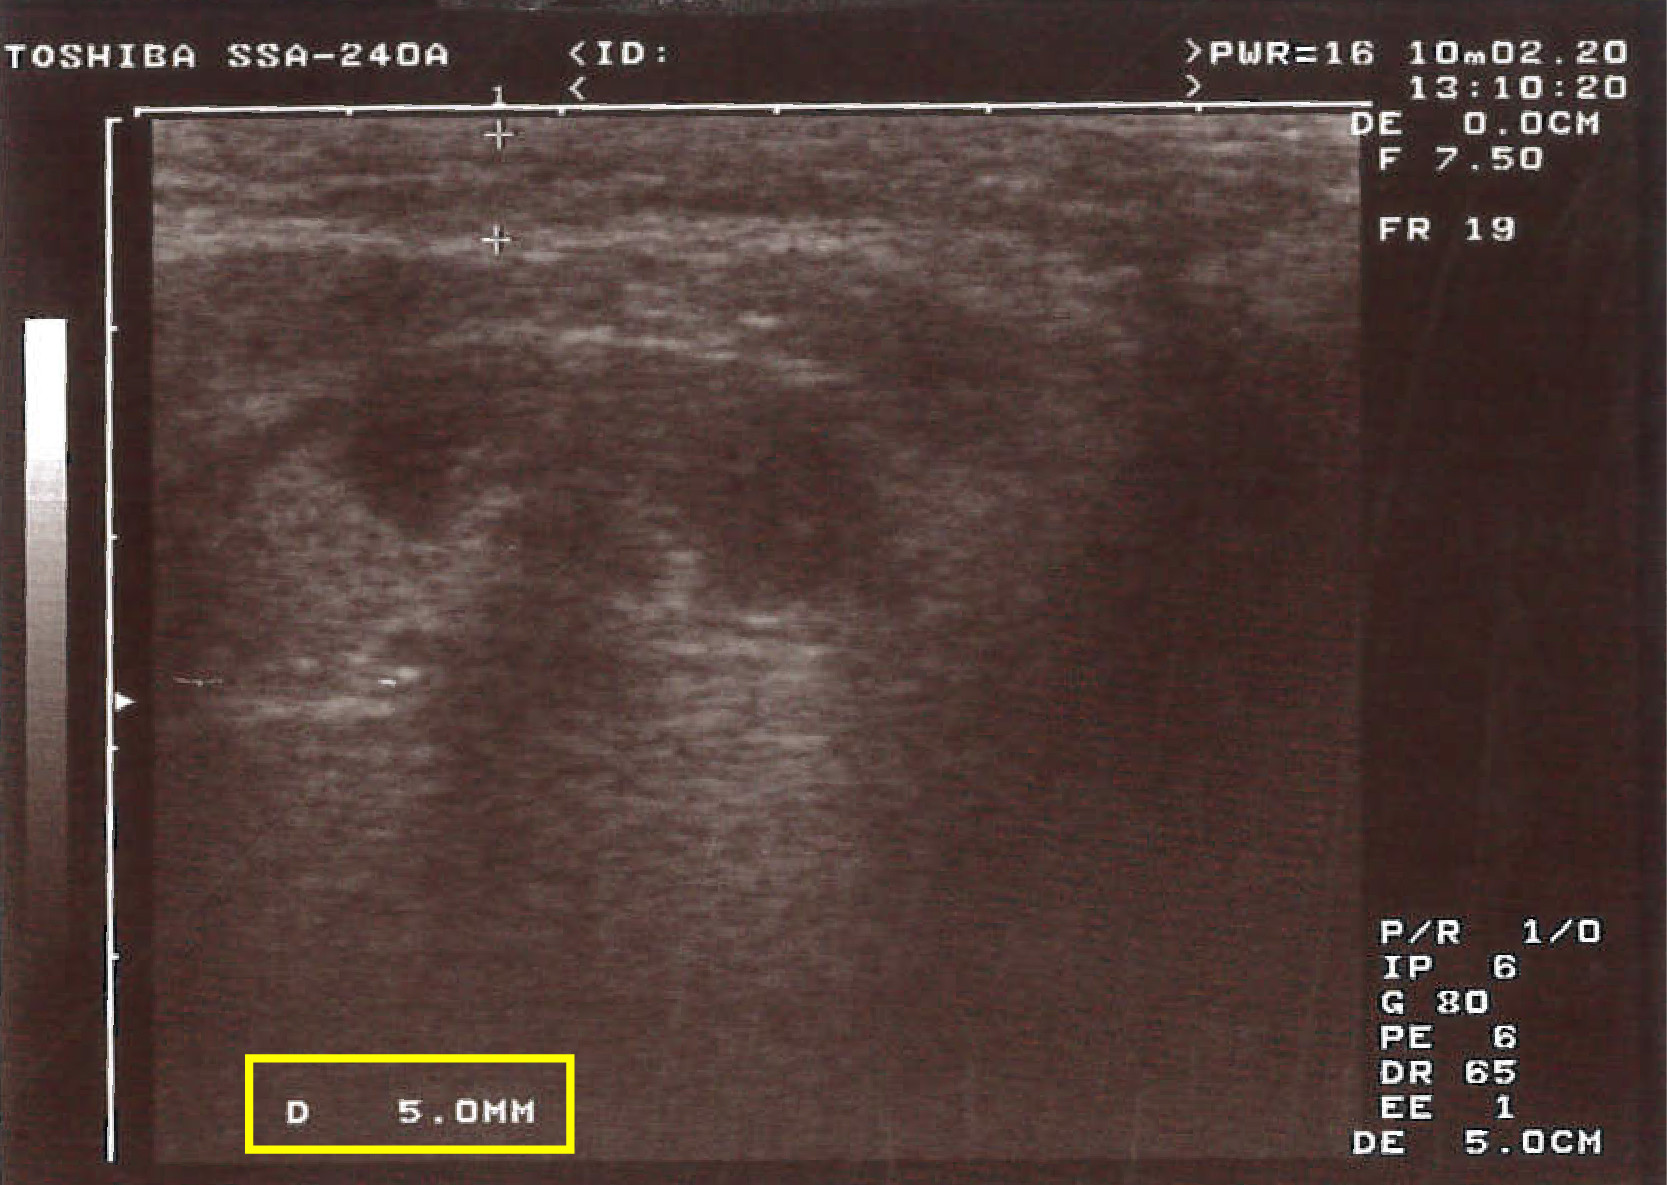

【超音波測脂 術後1個月】

一個月回診看術前、術後對比照,

OMG 真的有差!我其實只打一劑,

就已經減少 0.4 mm 厚度的脂肪呢 ~